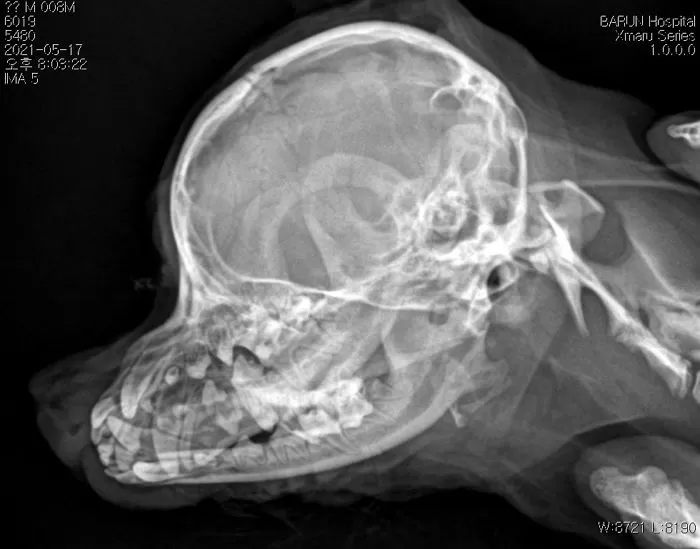

A씨는 놀란 마음에 집 근처 24시 동물 병원을 급히 찾아 이것저것 검사를 했더니 갈비늑골 3개가 부러져있고 두개골 파열에 복부 멍 자국, 신경계 이상 등 강아지의 몸 상태는 매우 처참했다.

검사 결과 두개골 골절로 인한 뇌출혈 및 우뇌 이상 소견을 받았다. 수의사는 "이런 외상은 단순 높은 곳에서 떨어져서 생길 수 있는 게 아닌 폭력이 상당히 의심된다"고 설명했다.